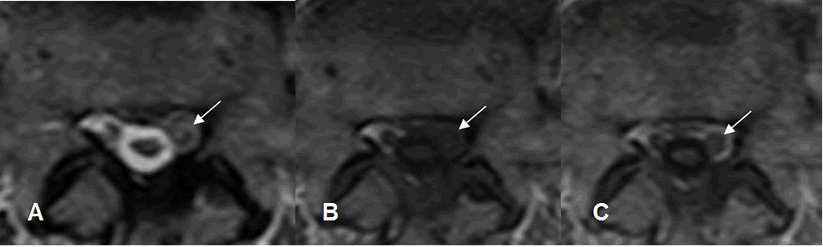

Fig 125. Fibrosis postquirúrgica.

A: RM axial en T2 y B: RM axial en T1. Obliteración de la grasa paramediana izquierda.

C: RM axial en T1 con contraste. Realce del contraste por fibrosis, que rodea una raíz engrosada.